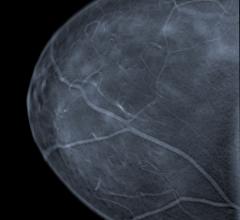

Early detection is an important and valuable tool in the continuing fight against breast cancer. Research has found that cancers discovered during early screening exams are often smaller in size and still confined to the breast compared to those found later. When considering these two factors, the size and spread of breast cancer — the most important predictors of prognosis for women with the disease — early detection has become a focal point in cancer care. As a result, the American Cancer Society (ACS) has established guidelines that recommend women over 40 undergo annual screening mammograms.

The majority of certified breast imaging facilities now have full-field digital mammography (FFDM) imaging systems. This is according to the U.S. Food and Drug Administration’s (FDA) data on the Mammography Quality Standards Act’s (MQSA) program and facilities.